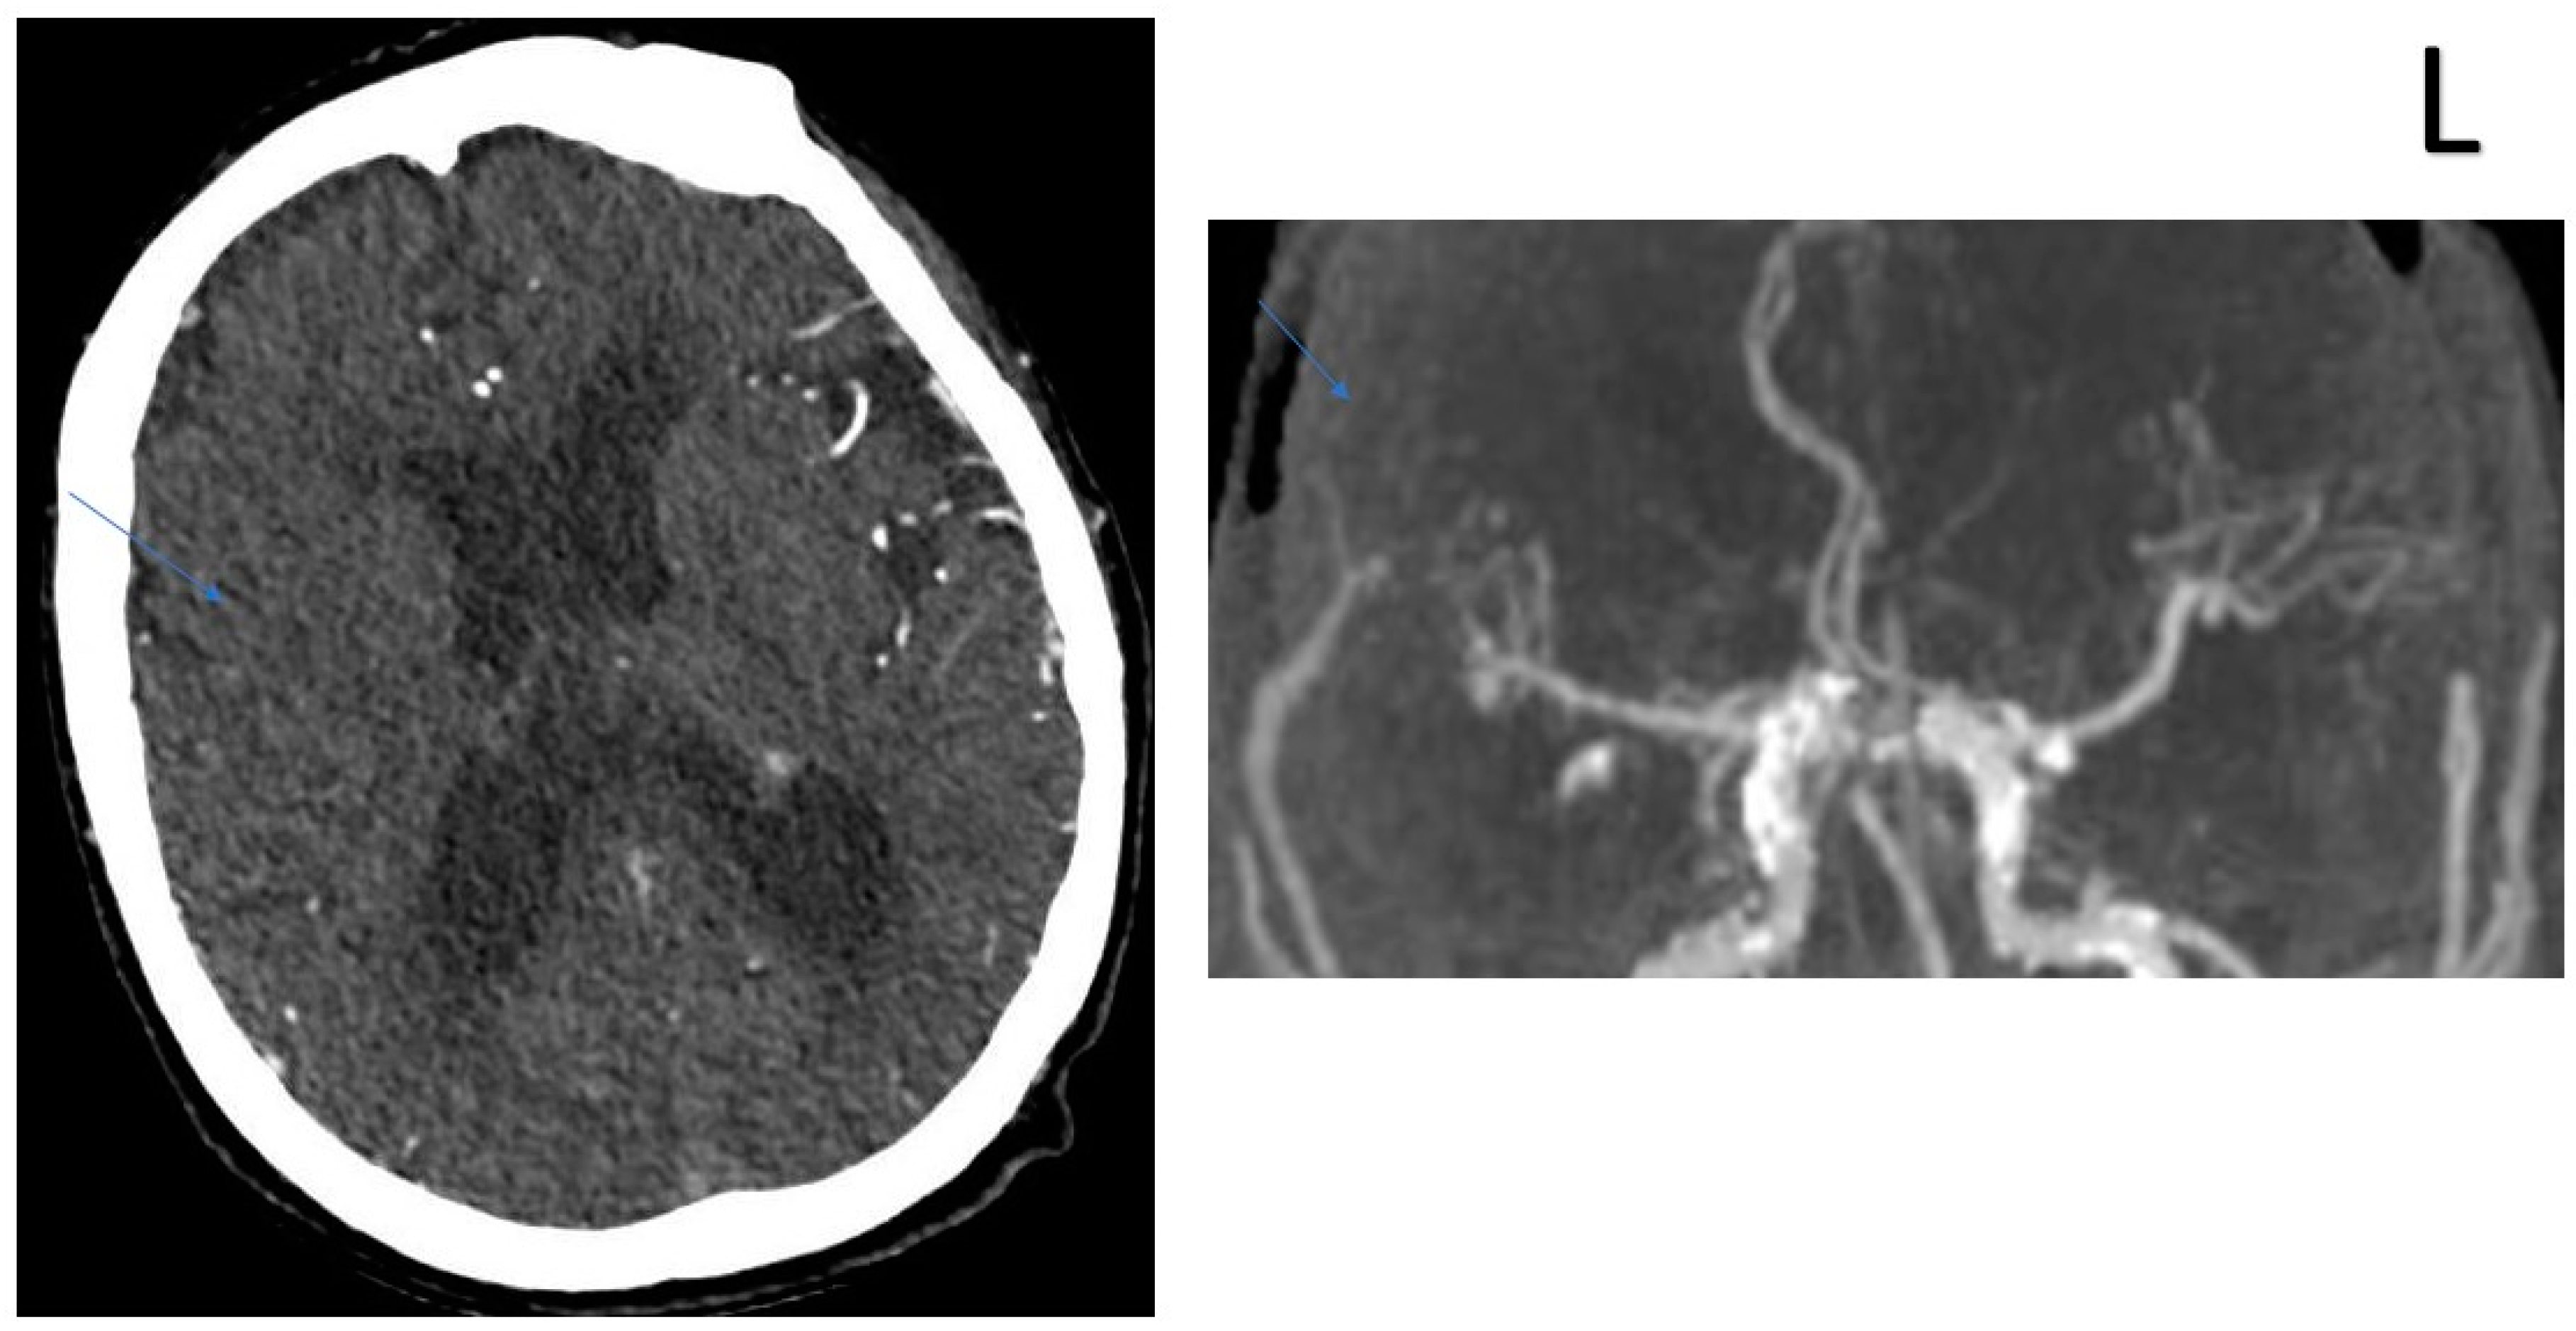

2.2. CT Protocol